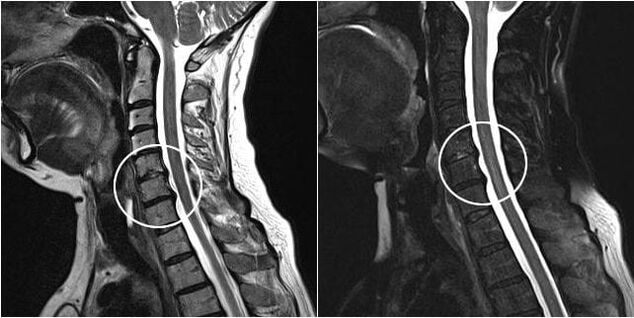

Indications for surgical intervention include the ineffectiveness of conservative treatment, as well as complications of cervical osteochondrosis, for example, discogenic myelopathy, vertebral artery syndrome, and radicular syndrome.To reduce the spinal cord, blood vessels, and spinal roots, the following operations are performed: